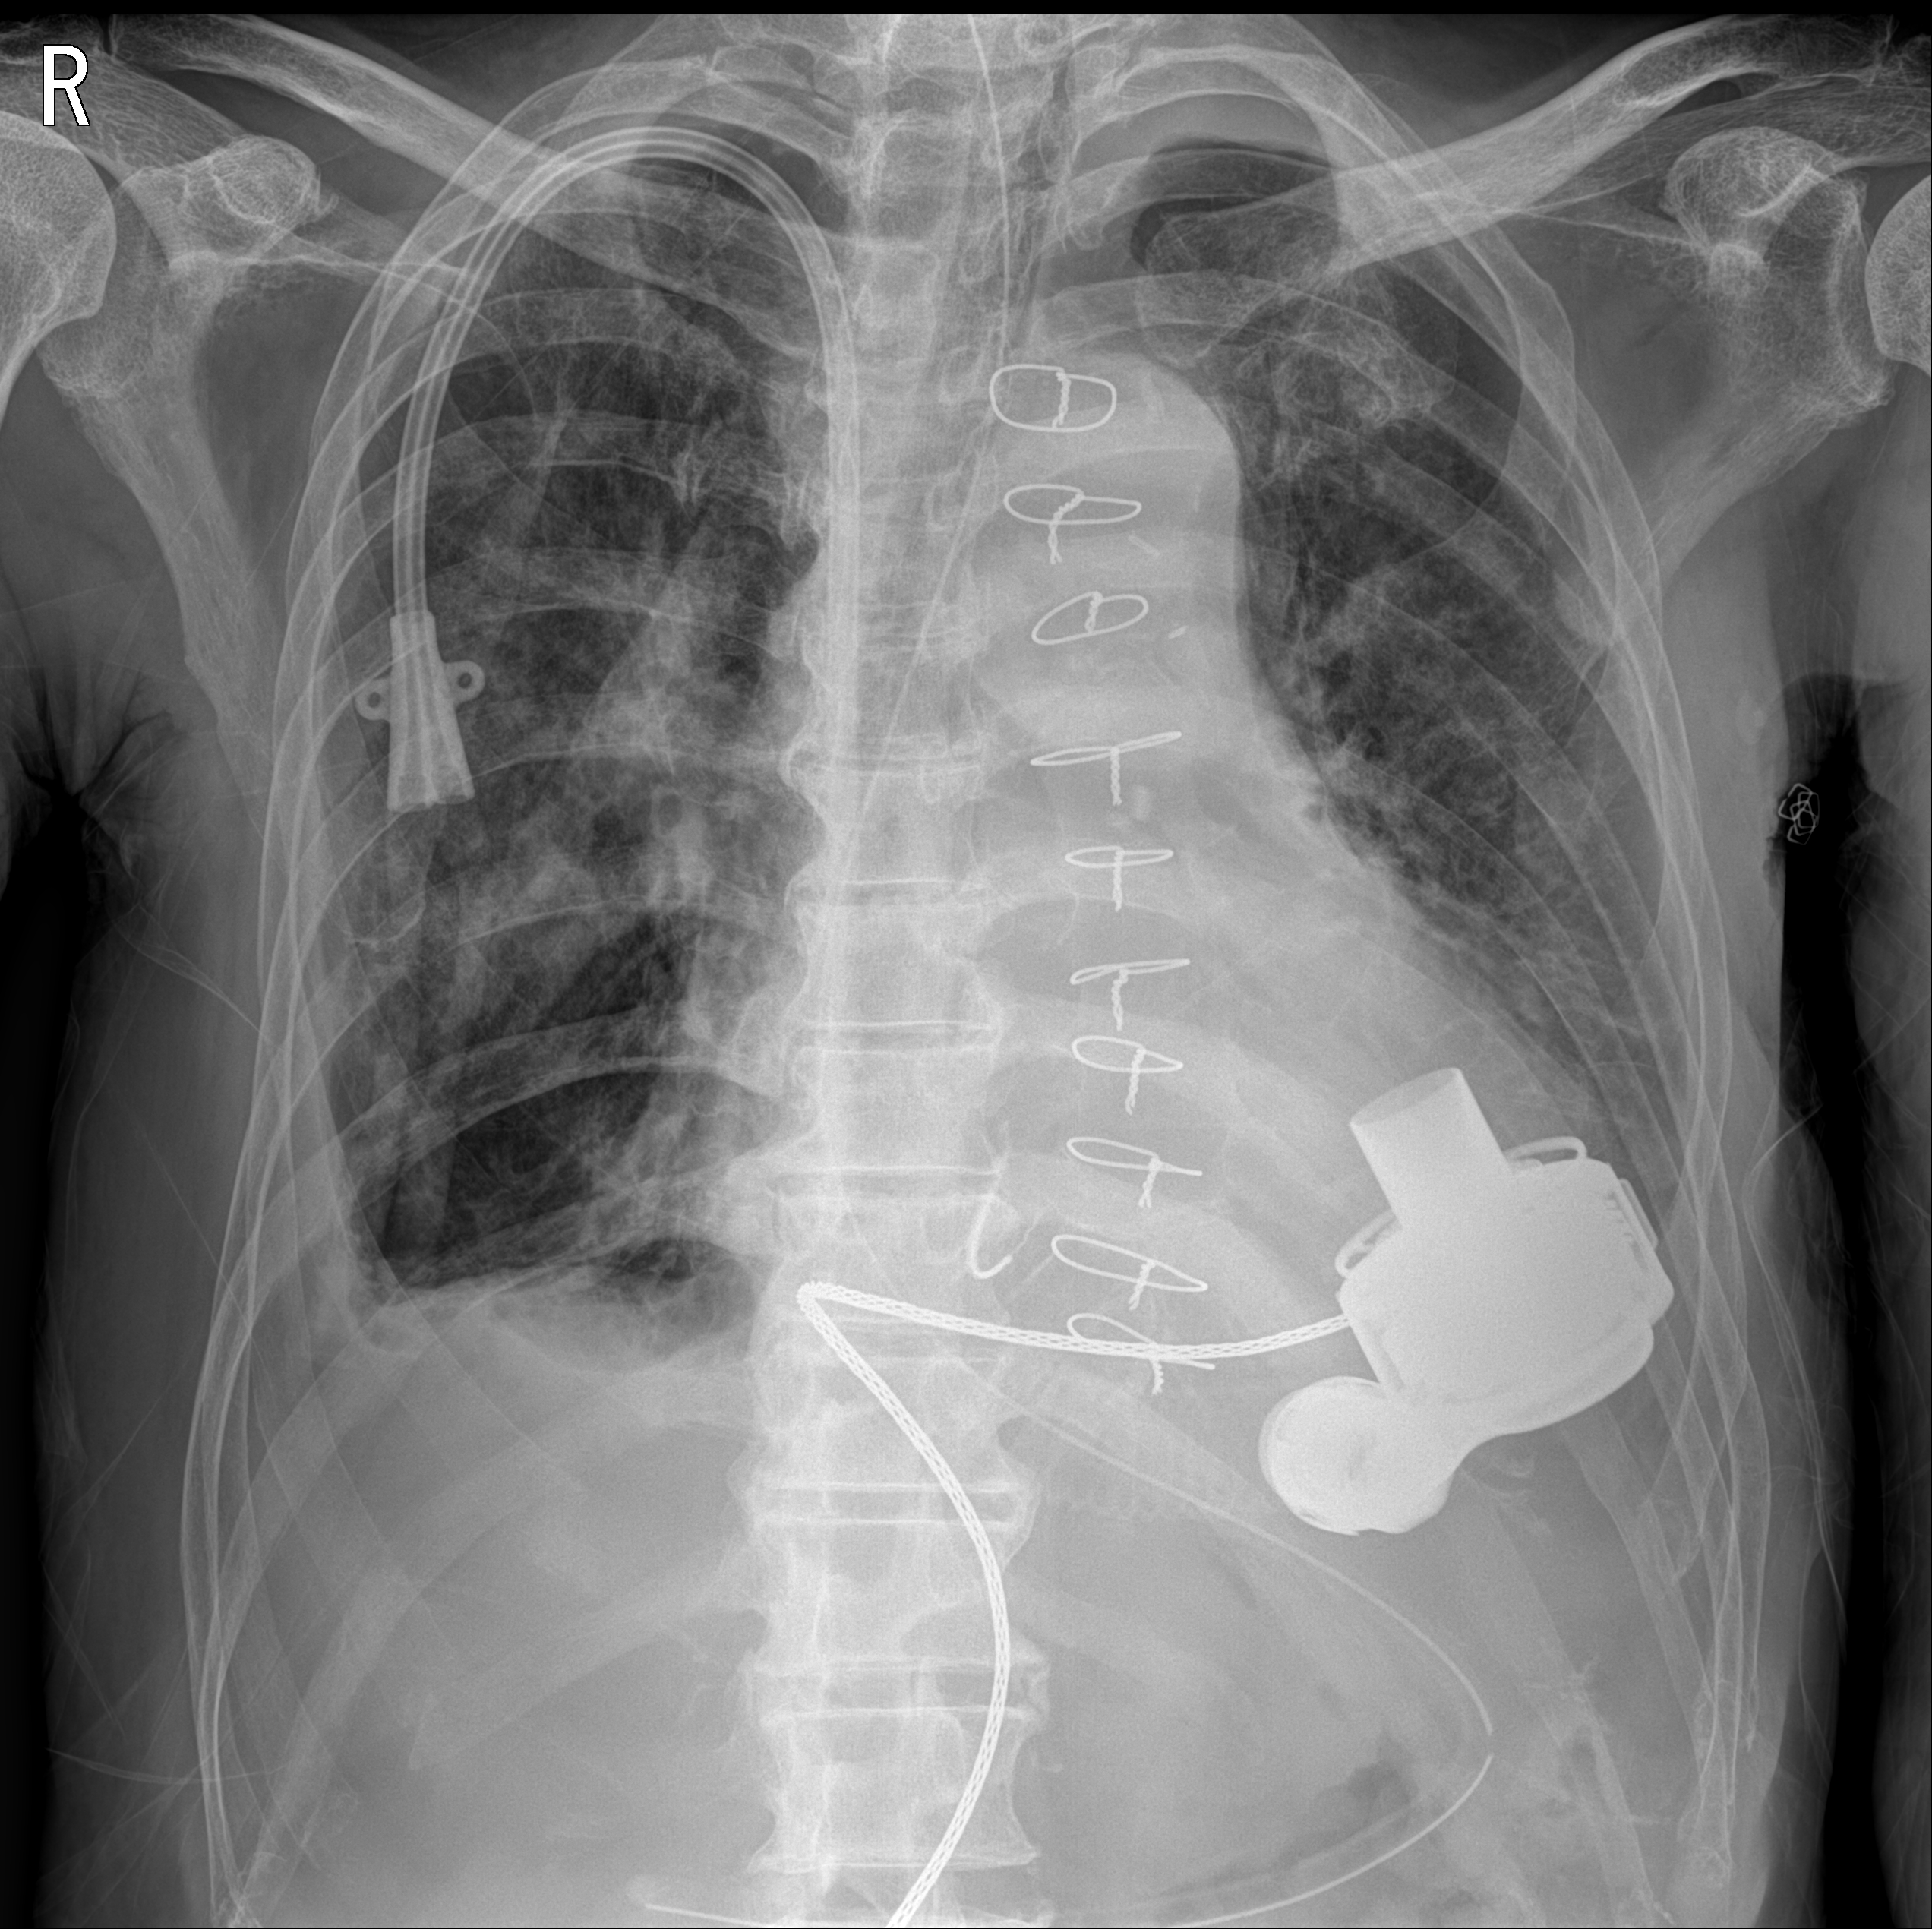

DCMP로 cardiogenic shock이 있어 VA ECMO, LV venting을 거처 LVAD (abbott사의 HeartMate 3) 적용하게 된 환자.

위와 같은 모양의 펌프를 좌심실의 첨부(LV apex)에 심어서 심장 자체를 bypass 하여 혈류를 대동맥 쪽으로 공급해 주게 된다.